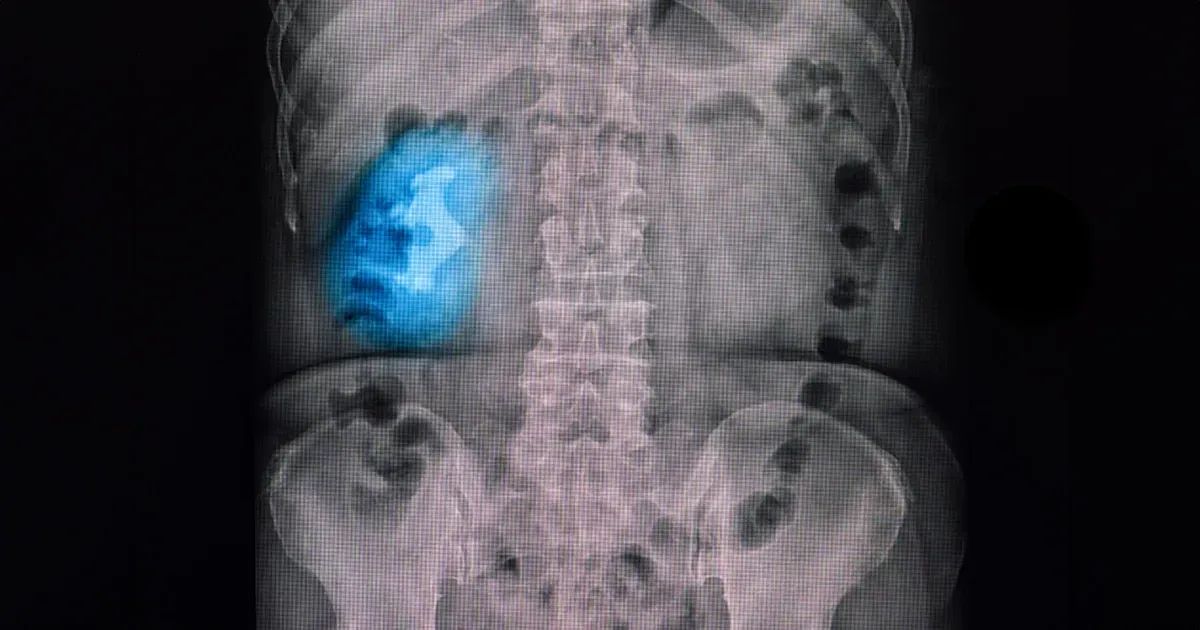

Istnieją cztery podstawowe rodzaje kamieni nerkowych — powstałe ze szczawianu wapnia, kwasu moczowego, struwitu lub cysteiny. Kamienie struwitowe (odlewowe) mają najbardziej charakterystyczny wygląd, gdyż tworzą duże, rozgałęzione struktury przypominające „poroże jelenia”, które wypełniają wewnętrzne przestrzenie nerek.

Połączenie tych zaburzeń metabolicznych ze złymi nawykami żywieniowymi lub odwodnieniem sprawia, że prawdopodobieństwo powstawania kamieni jest jeszcze większe. Diagnostyka kamicy odlewowej opiera się na badaniu moczu i badaniach obrazowych, które pozwalają ocenić zarówno obecność kamienia, jak i zakażenie. Badanie moczu pozwala wykryć bakterie i podwyższone pH, które są silnymi wskaźnikami rozwoju kamieni związanych z infekcją. Obrazowanie za pomocą promieni rentgenowskich, ultradźwięków lub tomografii komputerowej pozwala na ocenę kształtu, rozmiaru i położenia kamienia w nerce.